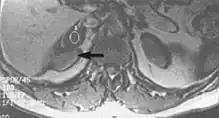

Metal artifacts occur at interfaces of tissues with different magnetic susceptibilities, which cause local magnetic fields to distort the external magnetic field. This distortion changes the precession frequency in the tissue leading to spatial mismapping of information. The degree of distortion depends on the type of metal (stainless steel having a greater distorting effect than titanium alloy), the type of interface (most striking effect at soft tissue-metal interfaces), pulse sequence and imaging parameters. Metal artifacts are caused by external ferromagnetics such as cobalt containing make-up, internal ferromagnetics such as surgical clips, spinal hardware and other orthopaedic devices, and in some cases, metallic objects swallowed by people with pica.[3] Manifestation of these artifacts is variable, including total signal loss, peripheral high signal and image distortion (Figs 3 and 4).[1] Reduction of these artifacts can be attempted by orientating the long axis of an implant or device parallel to the long axis of the external magnetic field, possible with mobile extremity imaging and an open magnet. Further methods used are choosing the appropriate frequency encoding direction, since metal artifacts are most pronounced in this direction, using smaller voxel sizes, fast imaging sequences, increased readout bandwidth and avoiding gradient-echo imaging when metal is present. A technique called MARS (metal artifact reduction sequence) applies an additional gradient, along the slice select gradient at the time the frequency encoding gradient is applied.